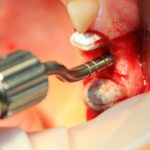

Синуслифтинг: что делать при перфорации слизистой оболочки гайморовой пазухи?